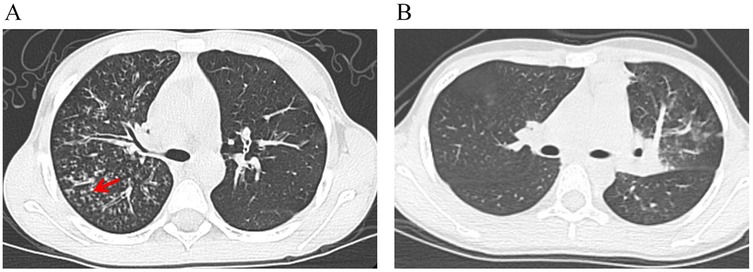

Background: Mycoplasma pneumoniae (MP) is a leading cause of community-acquired pneumonia in children, with a significant increase in incidence following the COVID-19 pandemic. The emergence of macrolide-resistant M. pneumoniae (MRMP) has complicated treatment, leading to the concept of macrolide-unresponsive M. pneumoniae pneumonia (MUMPP), defined as lack of improvement after 72 hours of macrolide therapy. Early identification of MUMPP is critical for timely intervention and improved outcomes. This study aimed to develop and validate a nomogram for early prediction of MUMPP in children. Methods: We conducted a retrospective study involving 278 pediatric patients with MP pneumonia, divided into training (n=188) and validation (n=90) sets. Demographic, clinical, laboratory, and chest CT imaging data were collected. Univariate and multivariate logistic regression analyses were used to identify independent predictors of MUMPP. A nomogram was constructed and validated using receiver operating characteristic (ROC) curves, calibration plots, and decision curve analysis (DCA). Results: Six independent predictors were identified: tree-in-bud pattern, neutrophil-value, lymphocyte-value, creatine kinase (CK), platelet-to-lymphocyte ratio (PLR), and male gender. The nomogram demonstrated strong discriminatory power, with area under the curve (AUC) values of 0.838 (95% CI: 0.779–0.897) in the training set and 0.835 (95% CI: 0.752–0.918) in the validation set. Calibration and DCA confirmed good clinical utility. Conclusion: We developed and validated a simple‐to‐use nomogram for predicting MUMPP in early stage. The nomogram demonstrates strong discriminatory power and calibration, and may be a practical tool for clinical practice.